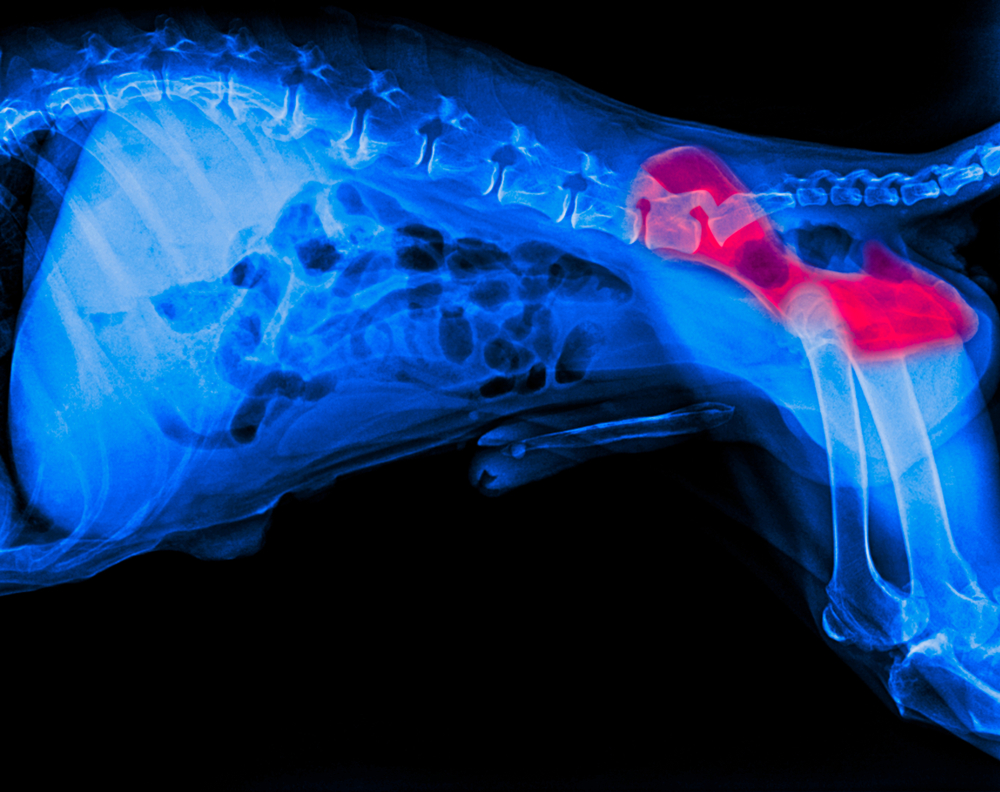

If you suspect your dog has hip dysplasia, contact our Family Veterinary Care of Oakdale team so we can perform your pup’s thorough examination. To diagnose this disorder, our team typically does a physical examination, takes X-rays and in some cases, additional advanced images, and performs joint palpation techniques. Once we definitively diagnose that your canine companion has hip dysplasia, our team may recommend the following treatment options:

Although any dog can develop hip dysplasia, the condition is a common skeletal disorder that primarily affects large- and giant-breed dogs. The condition causes abnormal hip development, resulting in an improper fit between the joint’s ball and socket. Over time, this misalignment leads to joint deterioration, resulting in pain and reduced mobility.